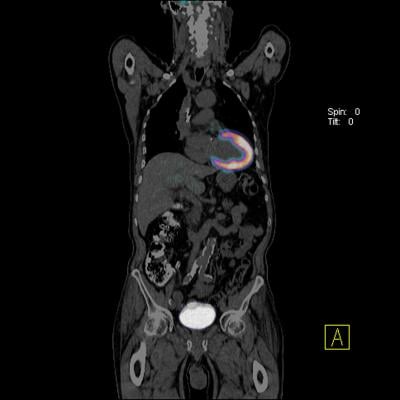

Positron emission tomography (PET) scans and computed tomography (CT) scans, as well as scans that combine information from each, have been used in the diagnosis of cardiac sarcoidosis, but the results are often unclear and hard to interpret, and lead to many false negatives.

A new combined PET-CT scan technique developed at UIC incorporates a 72-hour high-fat, low-sugar diet before images are taken. The new scan provides much clearer images of sarcoidosis and lets physicians better detect cardiac sarcoidosis. In a previous UIC study, researchers were able to diagnose cardiac sarcoidosis much more accurately and could diagnose cases that would not have been picked up using the usual 24-hour high-fat, low-sugar protocol normally prescribed before the combined PET-CT scans.

In the current study, the researchers used the new protocol to investigate the relationship between the presence of cardiac sarcoidosis and sarcoidosis in other parts of the body.

The researchers performed full-body (nose to knees) PET-CT scans of 188 patients who followed the 72-hour pre-test diet between Dec. 2014 and Dec. 2015 at the University of Illinois hospital, UI Health. Of the 20 scans that were positive for cardiac sarcoidosis, eight, or 40 percent, revealed sarcoidosis in other parts of the body.